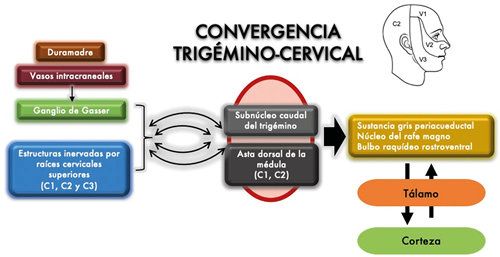

El mecanismo que determina la cefalea trigeminal no está claro. Sin embargo, constan datos que demuestran el protagonismo del sistema trigémino-vascular, las fibras nerviosas parasimpáticas y el hipotálamo (Figura 1). El sistema trigémino-vascular está compuesto por estructuras sensibles al dolor:

Fig. 1. Representación gráfica del sistema trigémino-vascular.

La neuralgia del trigémino es una afección que genera gran limitación en la calidad de vida de los pacientes que la padecen. Con el estudio de esta patología ha quedado claro que comprender la convergencia trigémino-cervical es fundamental para abordar de forma exitosa un plan terapéutico óptimo.

En el caso descrito, consideramos que la paciente presentó dos diagnósticos: una neuralgia del trigémino atribuida a lesión ocupante de espacio catalogada según la Clasificación Internacional de las Cefaleas (ICHD-3) (11) como neuralgia del trigémino atribuida a lesión ocupante de espacio y una neuralgia occipital. No obstante, el complejo trigémino-cervical podría explicar la coexistencia y solapamiento de ambos diagnósticos.

Entender el origen del funcionamiento de las células, vías de conducción, tejidos y sistemas de nuestro cuerpo, nos permite como especialistas en cualquier rama de la medicina tener un amplio espectro de herramientas y posibilidades de acción ante cualquier patología. Aunque los resultados en satisfacción y mejoría del dolor en nuestra paciente fueron en su mayoría transitorios con las diversas técnicas intervencionistas realizadas, es un caso que nos permitió apreciar e ilustrar las implicaciones anatómicas y fisiopatológicas de la cefalea trigeminal. Comprender las múltiples redes neuronales relacionadas con el complejo o la convergencia trigémino-cervical nos permitió plantear diversas alternativas en el enfoque terapéutico de la paciente, incrementando las posibilidades de acción en el abordaje del origen de la nocicepción generada por la neuralgia del trigémino, cuya etiología era en parte debida a la localización del tumor en el cavum de Meckel, asiento del ganglio de Gasser (12-14).